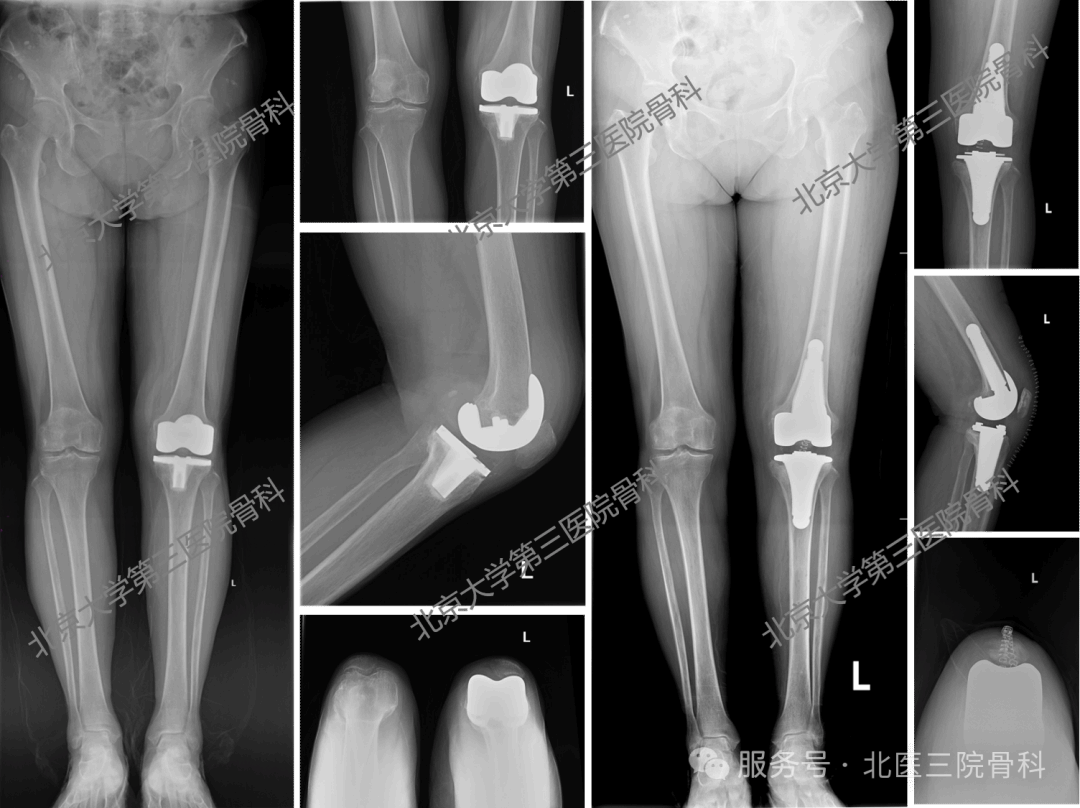

术前影像与术后影像